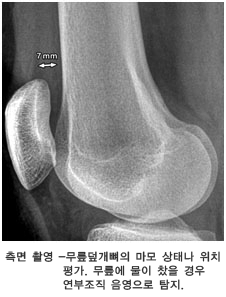

• 무릎의 엑스레이는 필수적으로 네 장을 찍는데 무릎 관절을 평가하는데 중요한 역할을 합니다.

퇴행성 관절염에 합당한 방사선 소견

• 관절의 모퉁이에 튀어나온 뼈돌기 (돌출된 뼈) - 가장 특징적인 소견

• 비대칭적으로 뼈사이 공간이 좁아지는 소견

• 연골밑의 뼈가 하얗게 되는 소견

• 골낭종

• 방사선 소견이 항상 증상의 심한 정도와 일치하지는 않아서 통증이 심한데도 불구하고 엑스레이 소견은 경미할 수도 있고 반대로 엑스레이 결과는 심한 관절염 변화를 보이는데도 환자는 큰 불편을 느끼지 않을 수도 있습니다.